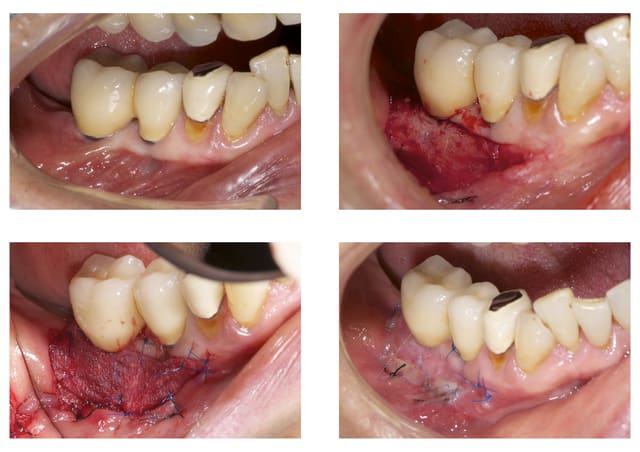

Premier cas de greffe "epthelio-conjonctive" au mucograft

Et d'ailleurs comment on la nomme dans ce cas cette greffe?

Sinon c'est plus rapide, moins douloureux, j'attends maintenant la cicatrisation complète.

Joli boulot. La dernière photo est combien de temps après la chirurgie ?

15 jours après, lors du retrait des sutures.

c'est pas flagrant sur la photo 2. Tu es en épaisseur totale ou partielle ?

Partielle.

Bon ben j'ai essayé, mais je ne le referai plus.

Résultat décevant.

Est-ce du fait de mon intervention ou du matériaux. J'ai tendance a croire que c'est plutôt à cause du mucograft.

J'ai aussi testé ainsi que le Mucoderm; dans les deux cas les résultats sont magnifiques à court terme et décevants sur le long terme...

Lors de la conférence d'Olivier à Paris, ce dernier avec DrMarcus avaient confirmé la chose ..

L'une des causes selon eux serait qu'il ne faudrait pas comprimer le "greffon" lors de la pose, ce qui est assez difficile à éviter lors des sutures ...

le résultat n'est pas si nul,surtout vu les contraintes opératoires en mandibulaire postérieur